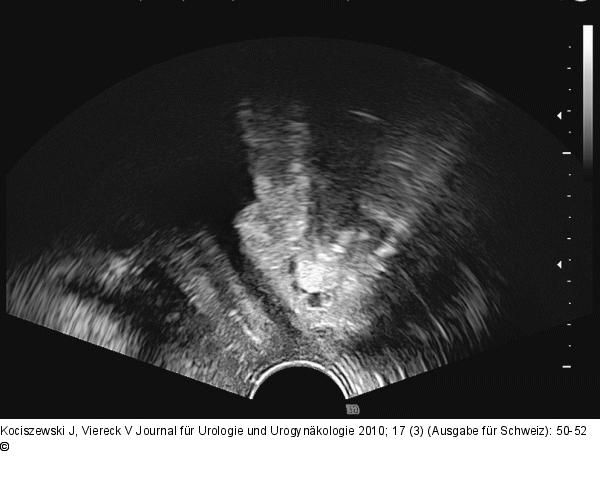

Abbildung 3: TVT-Band Wichtig zur Beurteilung der TVT-Position: Kontrolle in der zweiten Ebene (Sagittalschnitt). |

Abbildung 3: TVT-Band

Wichtig zur Beurteilung der TVT-Position: Kontrolle in der zweiten Ebene (Sagittalschnitt). |